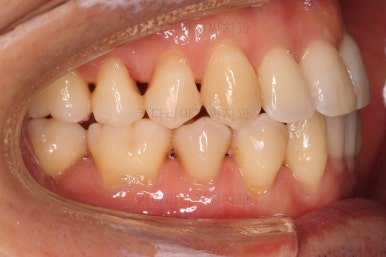

부산비수술교정 키다리아저씨치과에서 시행한 이번 치료의 결과입니다.

옆모습이 주걱턱 느낌이 많이 없어졌고 볼록하던 아랫입술도 뒤로 들어갔어요. 앞니가 거꾸로 물리지 않게 되어 웃거나 말하는 모습도 자연스러워졌어요.

아랫니 갯수가 모자라고 중앙이 맞지 않았고 짝이 안맞는 상황이었으나 비교적 잘 마무리를 했어요.

거꾸로 물리는 상황이 개선되었기 때문에 앞니나 어금니의 교합은 이전과 비교할 수 없을만큼 좋아졌지요.

전후 모습을 비교해 보겠습니다.

왼쪽이 치료 전, 오른쪽이 치료 후 모습입니다.